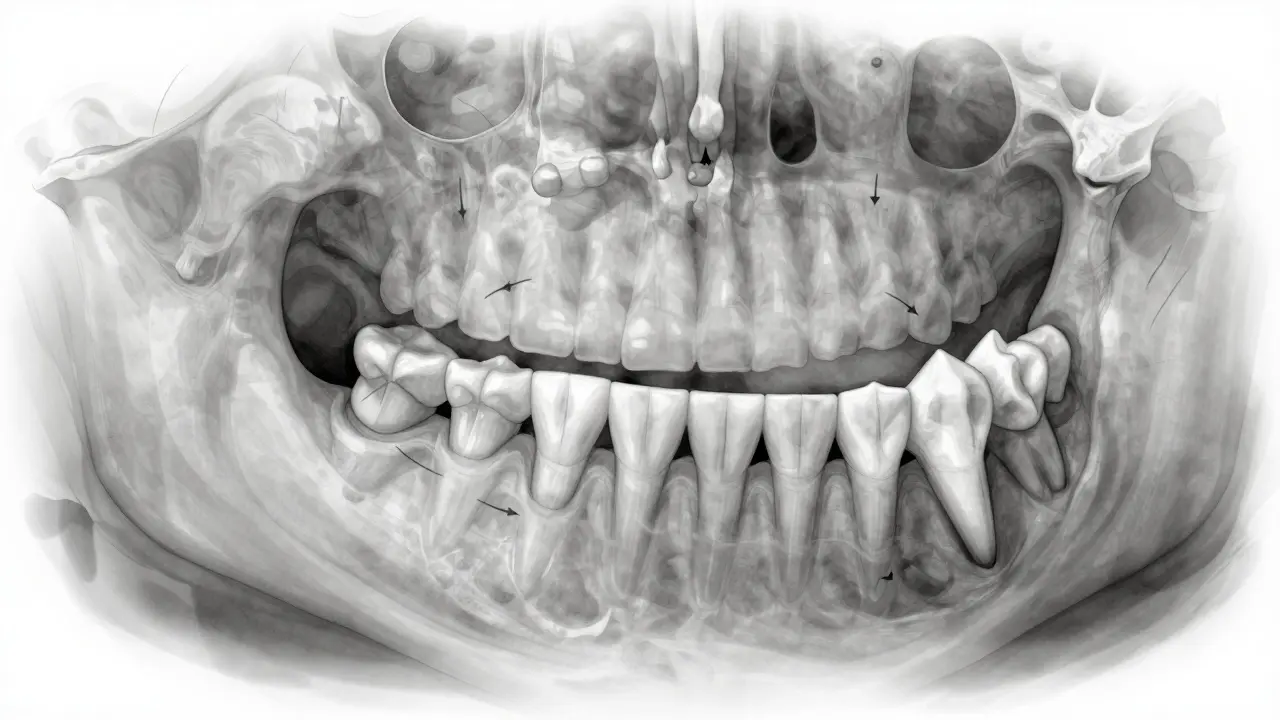

Příčinný řez čelistí s posunutými zuby do prázdného místa po ztrátě zubu.

Když ztratíte trvalý zub - třeba kvůli úrazu, kazu nebo parodontitidě - a necháte prázdné místo, ostatní zuby se začnou posouvat. Zuby vedle prázdného místa se nakloní dovnitř, zuby naproti vyrůstají ven. Výsledek? Zuby se překrývají, vznikají mezery, změní se příkryt. To může způsobit problémy s čištěním, zvýšené riziko kazu a dokonce i ztrátu dalších zubů.

Proto je důležité, aby se chybějící zub nahradil co nejdříve - buď náhradou, implantací nebo mostem. I když se vám zdá, že to není vidět, vnitřní struktura čelisti se mění. Kosti se začnou rozpadat, zuby se posunou a opravit to později je mnohem složitější a dražší.

Než začnete s léčbou, lékař provede rentgen, vyfotí vaše ústy a udělá model čelisti. Pak vám řekne, co je příčinou vašeho postavení zubů - a jak to opravit. Někdy stačí jen odstranit návyk, jako je tlačení jazykem. Někdy je potřeba odstranit zuby, aby se vytvořilo místo. A někdy je nutné kombinovat ortodoncii s chirurgickým zákrokem.